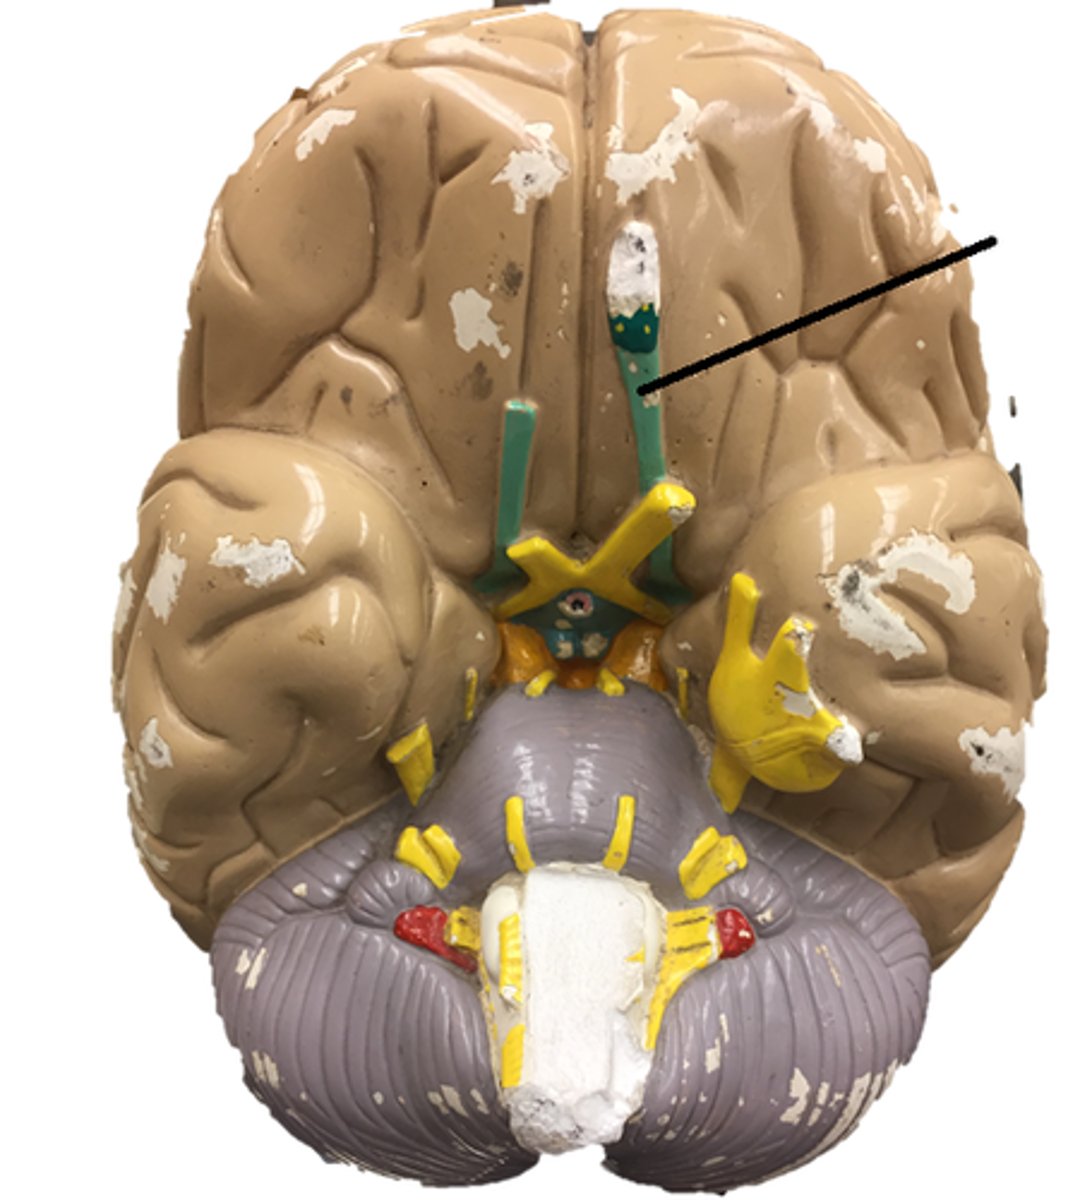

longitudinal fissure

corpus callosum

septum pellucidum

falx cerebri